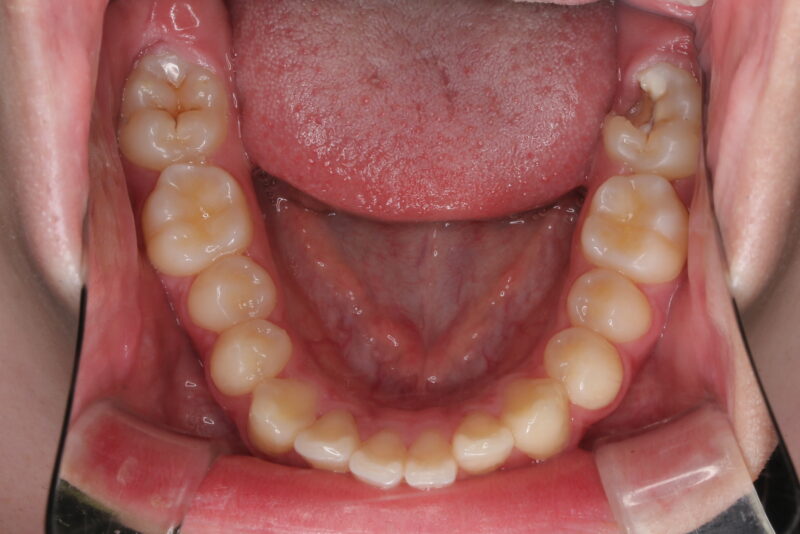

【術前口腔内写真】

右上の歯が1/4ほど虫歯で無くなっていることが分かります。